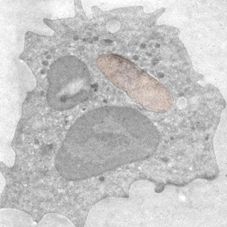

Neutrophiler Granulozyt infiziert mit E. Coli Bakterien (braun)